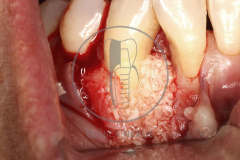

Tratamiento de defectos periodontales infraóseos en sector antero-inferior empleando gel de amelogeninas (Emdogain®) en combinación con un aloinjerto óseo (Biobank®). Paciente de 64 años, sin problemas médicos de relevancia, que presenta una periodontitis leve generalizada, pero asociada a presencia de defectos óseos verticales profundos a nivel de los espacios interdentales entre los caninos y los incisivos laterales inferiores. Tras la pertinente fase higiénica, se llevó a cabo una cirugía periodontal regenerativa, en la que, tras eliminar el cálculo subgingival (factor causal), se empleó una combinación de amelogeninas con un aloinjerto, para promover la regeneración tisular del periodonto perdido. Las imágenes clínicas y radiológicas, al año de seguimiento, reflejan un resultado terapéutico óptimo, con regeneración completa del tejido periodontal y mejora del pronóstico de los dientes involucrados.